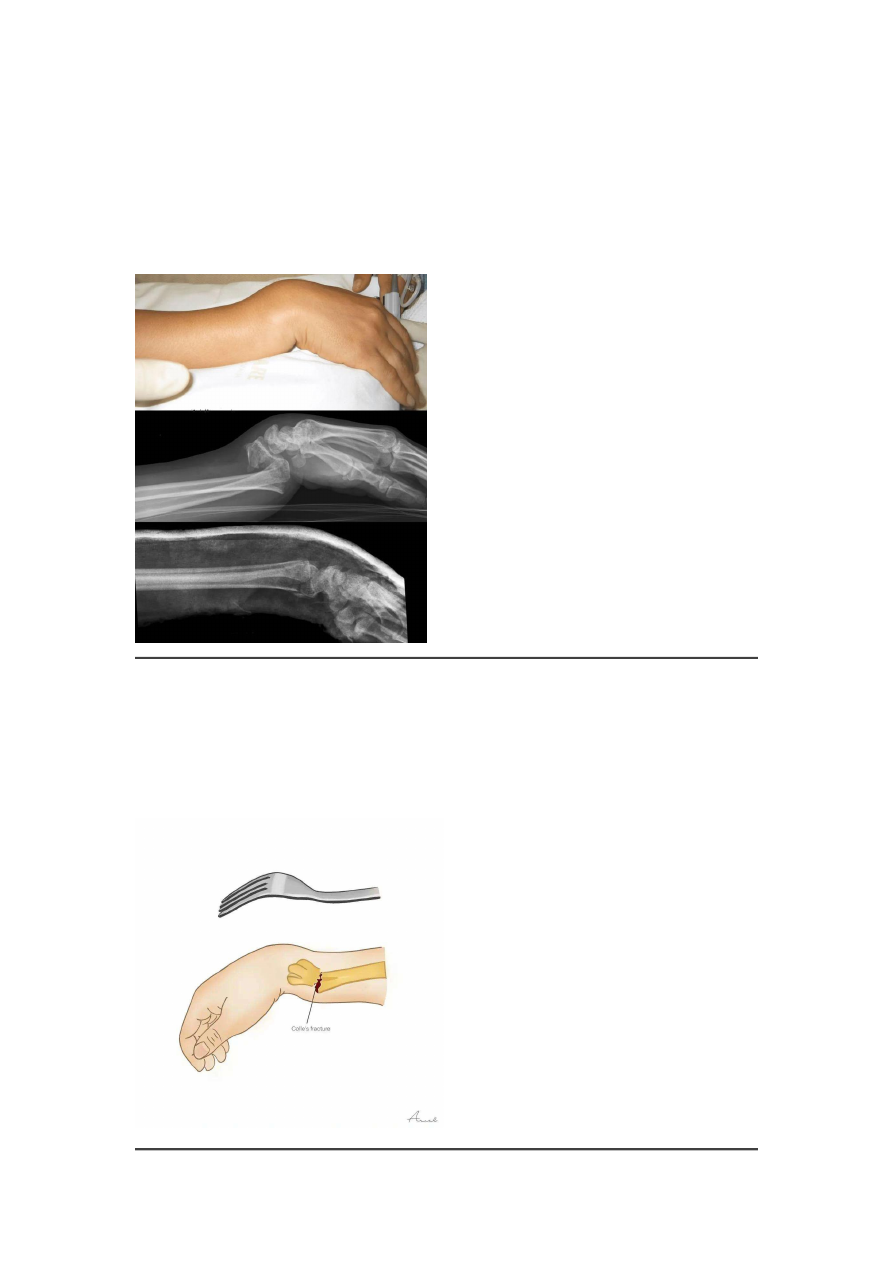

骨折远端向背侧移位:形成典型的

"

餐叉样

畸形

典型畸形:侧面观呈

,正面观呈

枪刺样